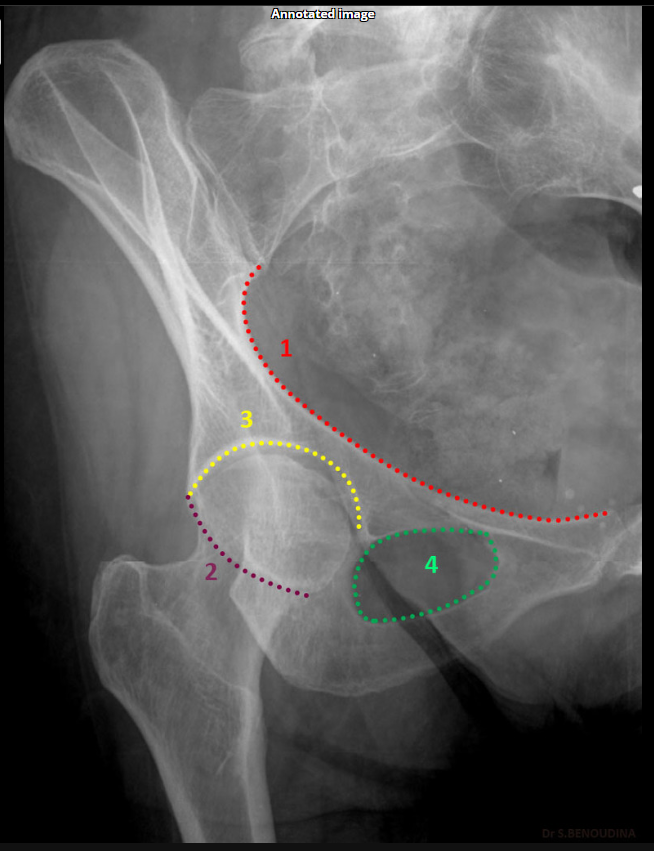

Which acetabular rim does the internal oblique Judet view show?

Posterior rim. (SHOWN #2 PURPLE)

<p>Posterior rim. (SHOWN #2 PURPLE)</p>

Anterior column. (SHOWN #1 RED)

<p>Anterior column. (SHOWN #1 RED)</p>

What does the iliopubic line represent in Judet views?

Anterior column.(SHOWN #1 RED)

<p>Anterior column.(SHOWN #1 RED)</p>

What does the ilioischial line represent in Judet views?

Posterior column.(SHOWN #1, ORANGE)

<p>Posterior column.(SHOWN #1, ORANGE)</p>